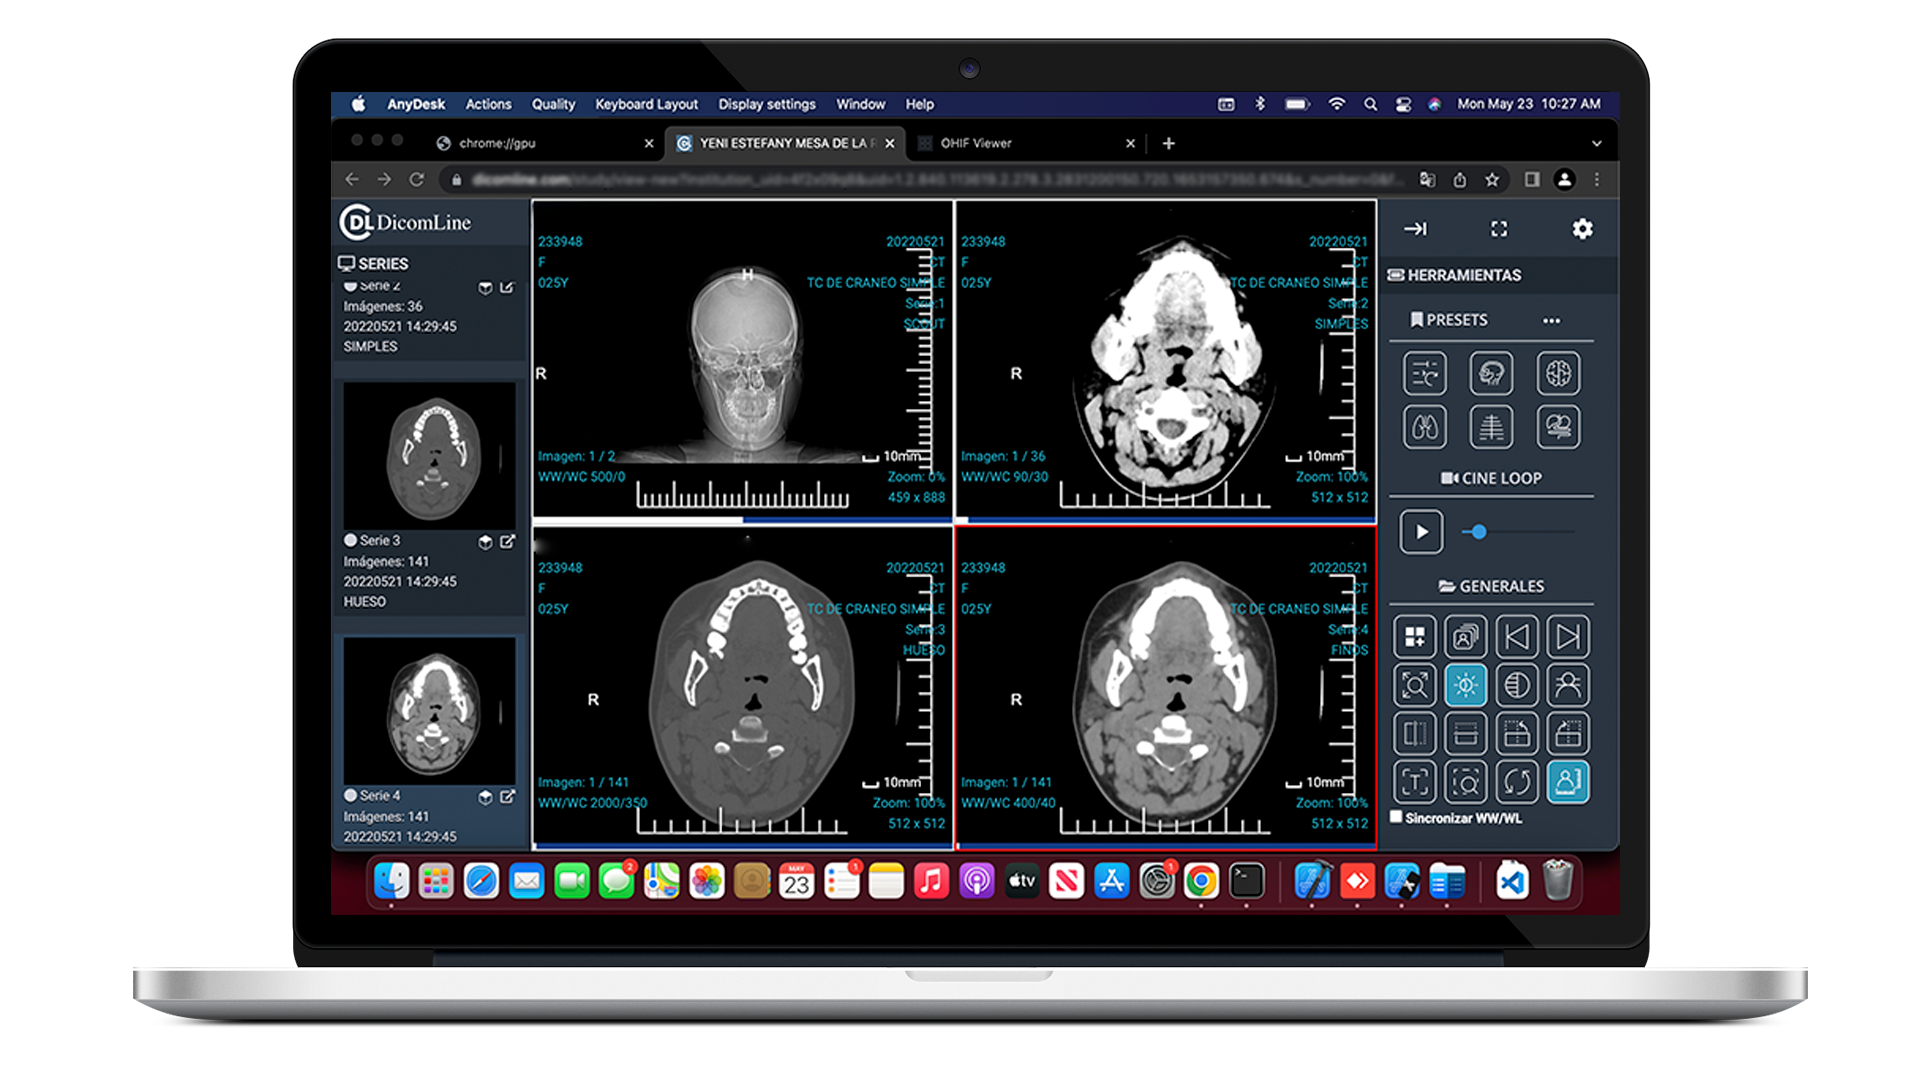

Experiencia de Usuario Superior

Interfaz intuitiva diseñada por médicos para médicos. Flujos de trabajo optimizados que reducen clicks, tiempo de carga ultra-rápido y herramientas que se adaptan a tu manera de trabajar.

Véalo en acción

Experimente el poder de nuestra plataforma a través de estas demostraciones interactivas.

Visor Web Optimizado

Al escanear, se abre un visor ligero y potente directamente en el navegador del móvil, permitiendo ver imágenes y reportes al instante.